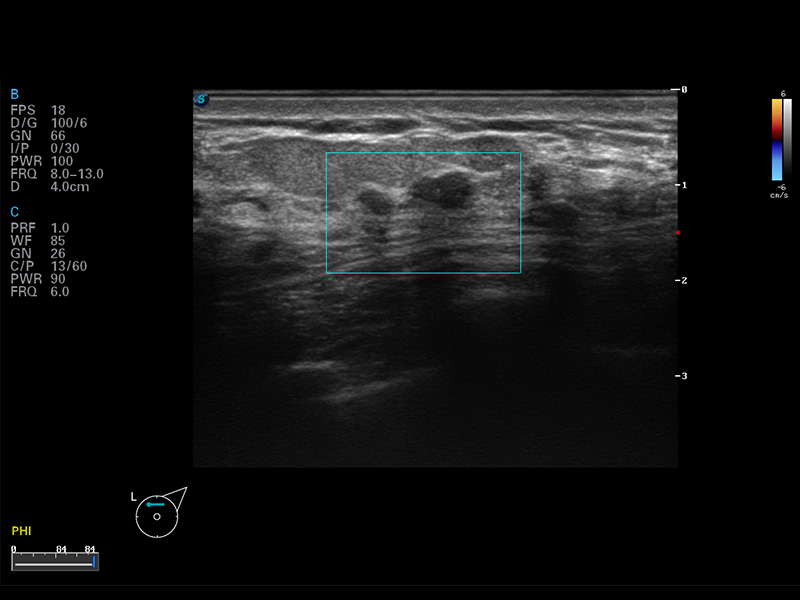

成像技术

多波束形成器

μ-Scan微米成像

谐波成像

实时宽景成像

空间复合成像